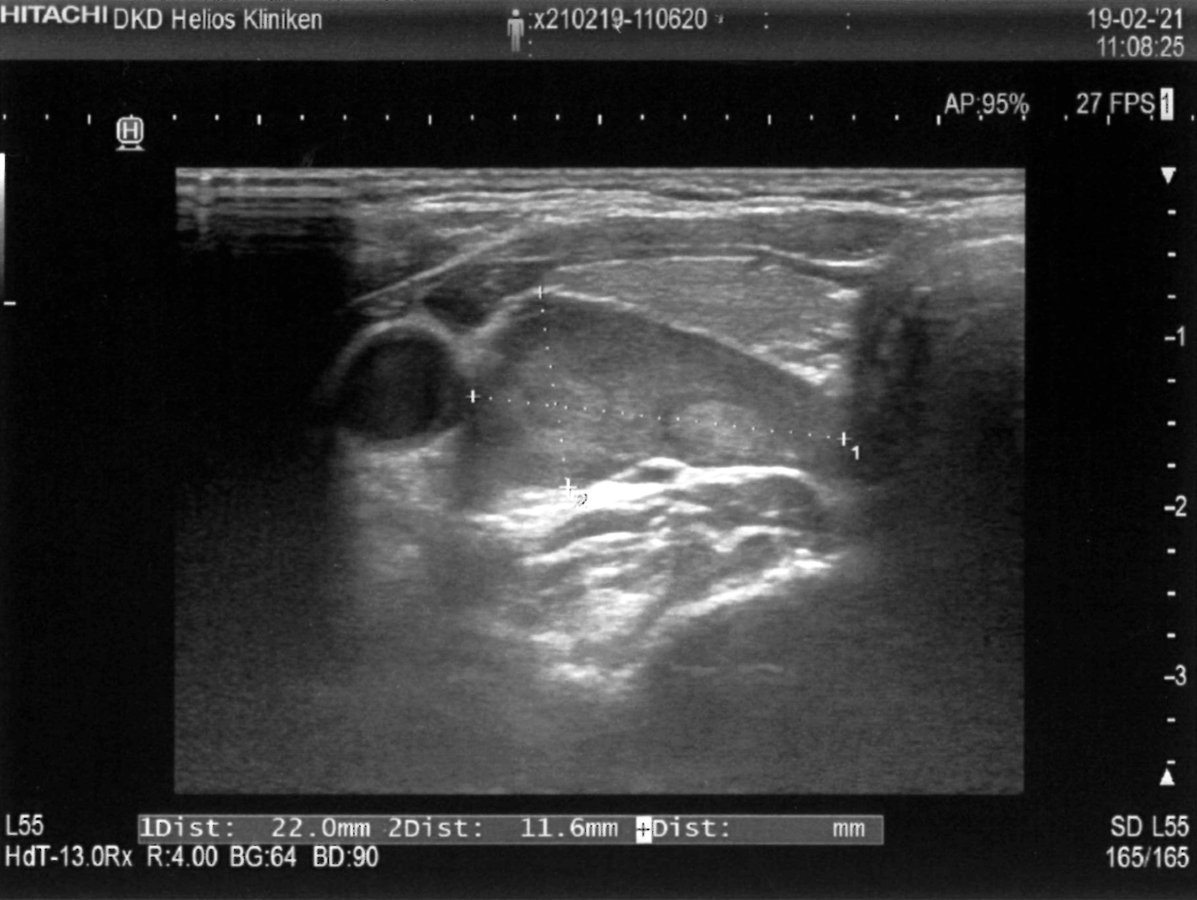

Der Ultraschall ist die Standard­untersuchungsmethode zur Lokalisations­diagnostik. Gleichzeitig kann damit auch die Schilddrüse untersucht werden. Hier ist ein Nebenschilddrüsenadenom zu erkennen (sagittal). Der Ultraschall ist die Standard­untersuchungsmethode zur Lokalisations­diagnostik. Gleichzeitig kann damit auch die Schilddrüse untersucht werden. Hier ist ein Nebenschilddrüsenadenom zu erkennen (sagittal). © DKD Klinik Wiesbaden

Einzige kurative Option beim primären Hyperparathyreoidismus (PHPT) ist die Resektion des pathologisch veränderten Nebenschilddrüsengewebes. Die OP ist auch bei asymptomatischen Patienten unter 50 Jahren bzw. mit Begleitbefunden wie Hyperkalzämie oder erniedrigter Knochendichte indiziert. Eine erfolgreiche Resektion senkt langfristig das erhöhte kardiovaskuläre Risiko. Deshalb wird geraten, alle Patienten einem Spezialisten für endokrine Chirurgie vorzustellen. Bei der Operationsplanung hilft eine Lokalisationsdia­gnostik der Nebenschilddrüsen. Sie erfolgt sonographisch – meist in Verbindung mit einer MIBI-Szintigraphie. Zusätzlich wird eine Schilddrüsenuntersuchung empfohlen.

• 1 vergrößerte Nebenschilddrüse im Ultraschall